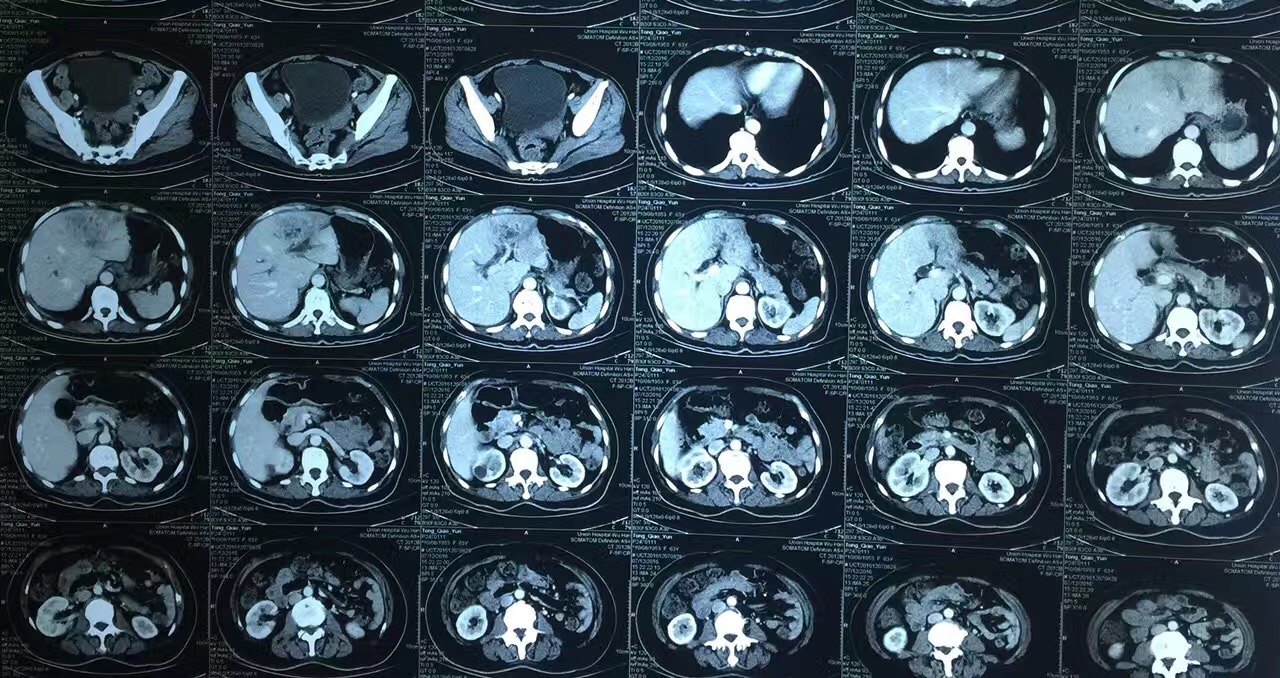

弥漫性脂肪肝伴正常肝岛一例ct增强病例

增强扫描,肝岛表现与脂肪浸润区同步均匀强化.